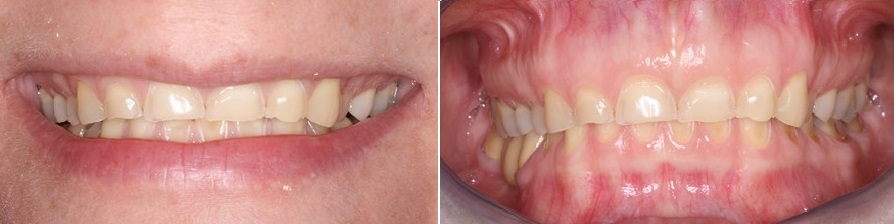

Στην φωτογραφία που ακολουθεί βλέπουμε το χαμόγελο της ασθενούς και πως αυτό μεταμορφώνεται σε λίγα λεπτά με την διαδικασία του mock up

Διάβρωση δοντιών- θεραπεία

Στην φωτογραφία που ακολουθεί βλέπουμε την εικόνα του χαμόγελου και του κάτω τριτημορίου του προσώπου πριν και μετά την αύξηση της κάθετης διάστασης του προσώπου με προσωρινές αποκαταστάσεις ρητίνης που τοποθετήθηκαν στα πίσω δόντια και των δύο γνάθων και είναι αντίγραφα του διαγνωστικού κερώματος.